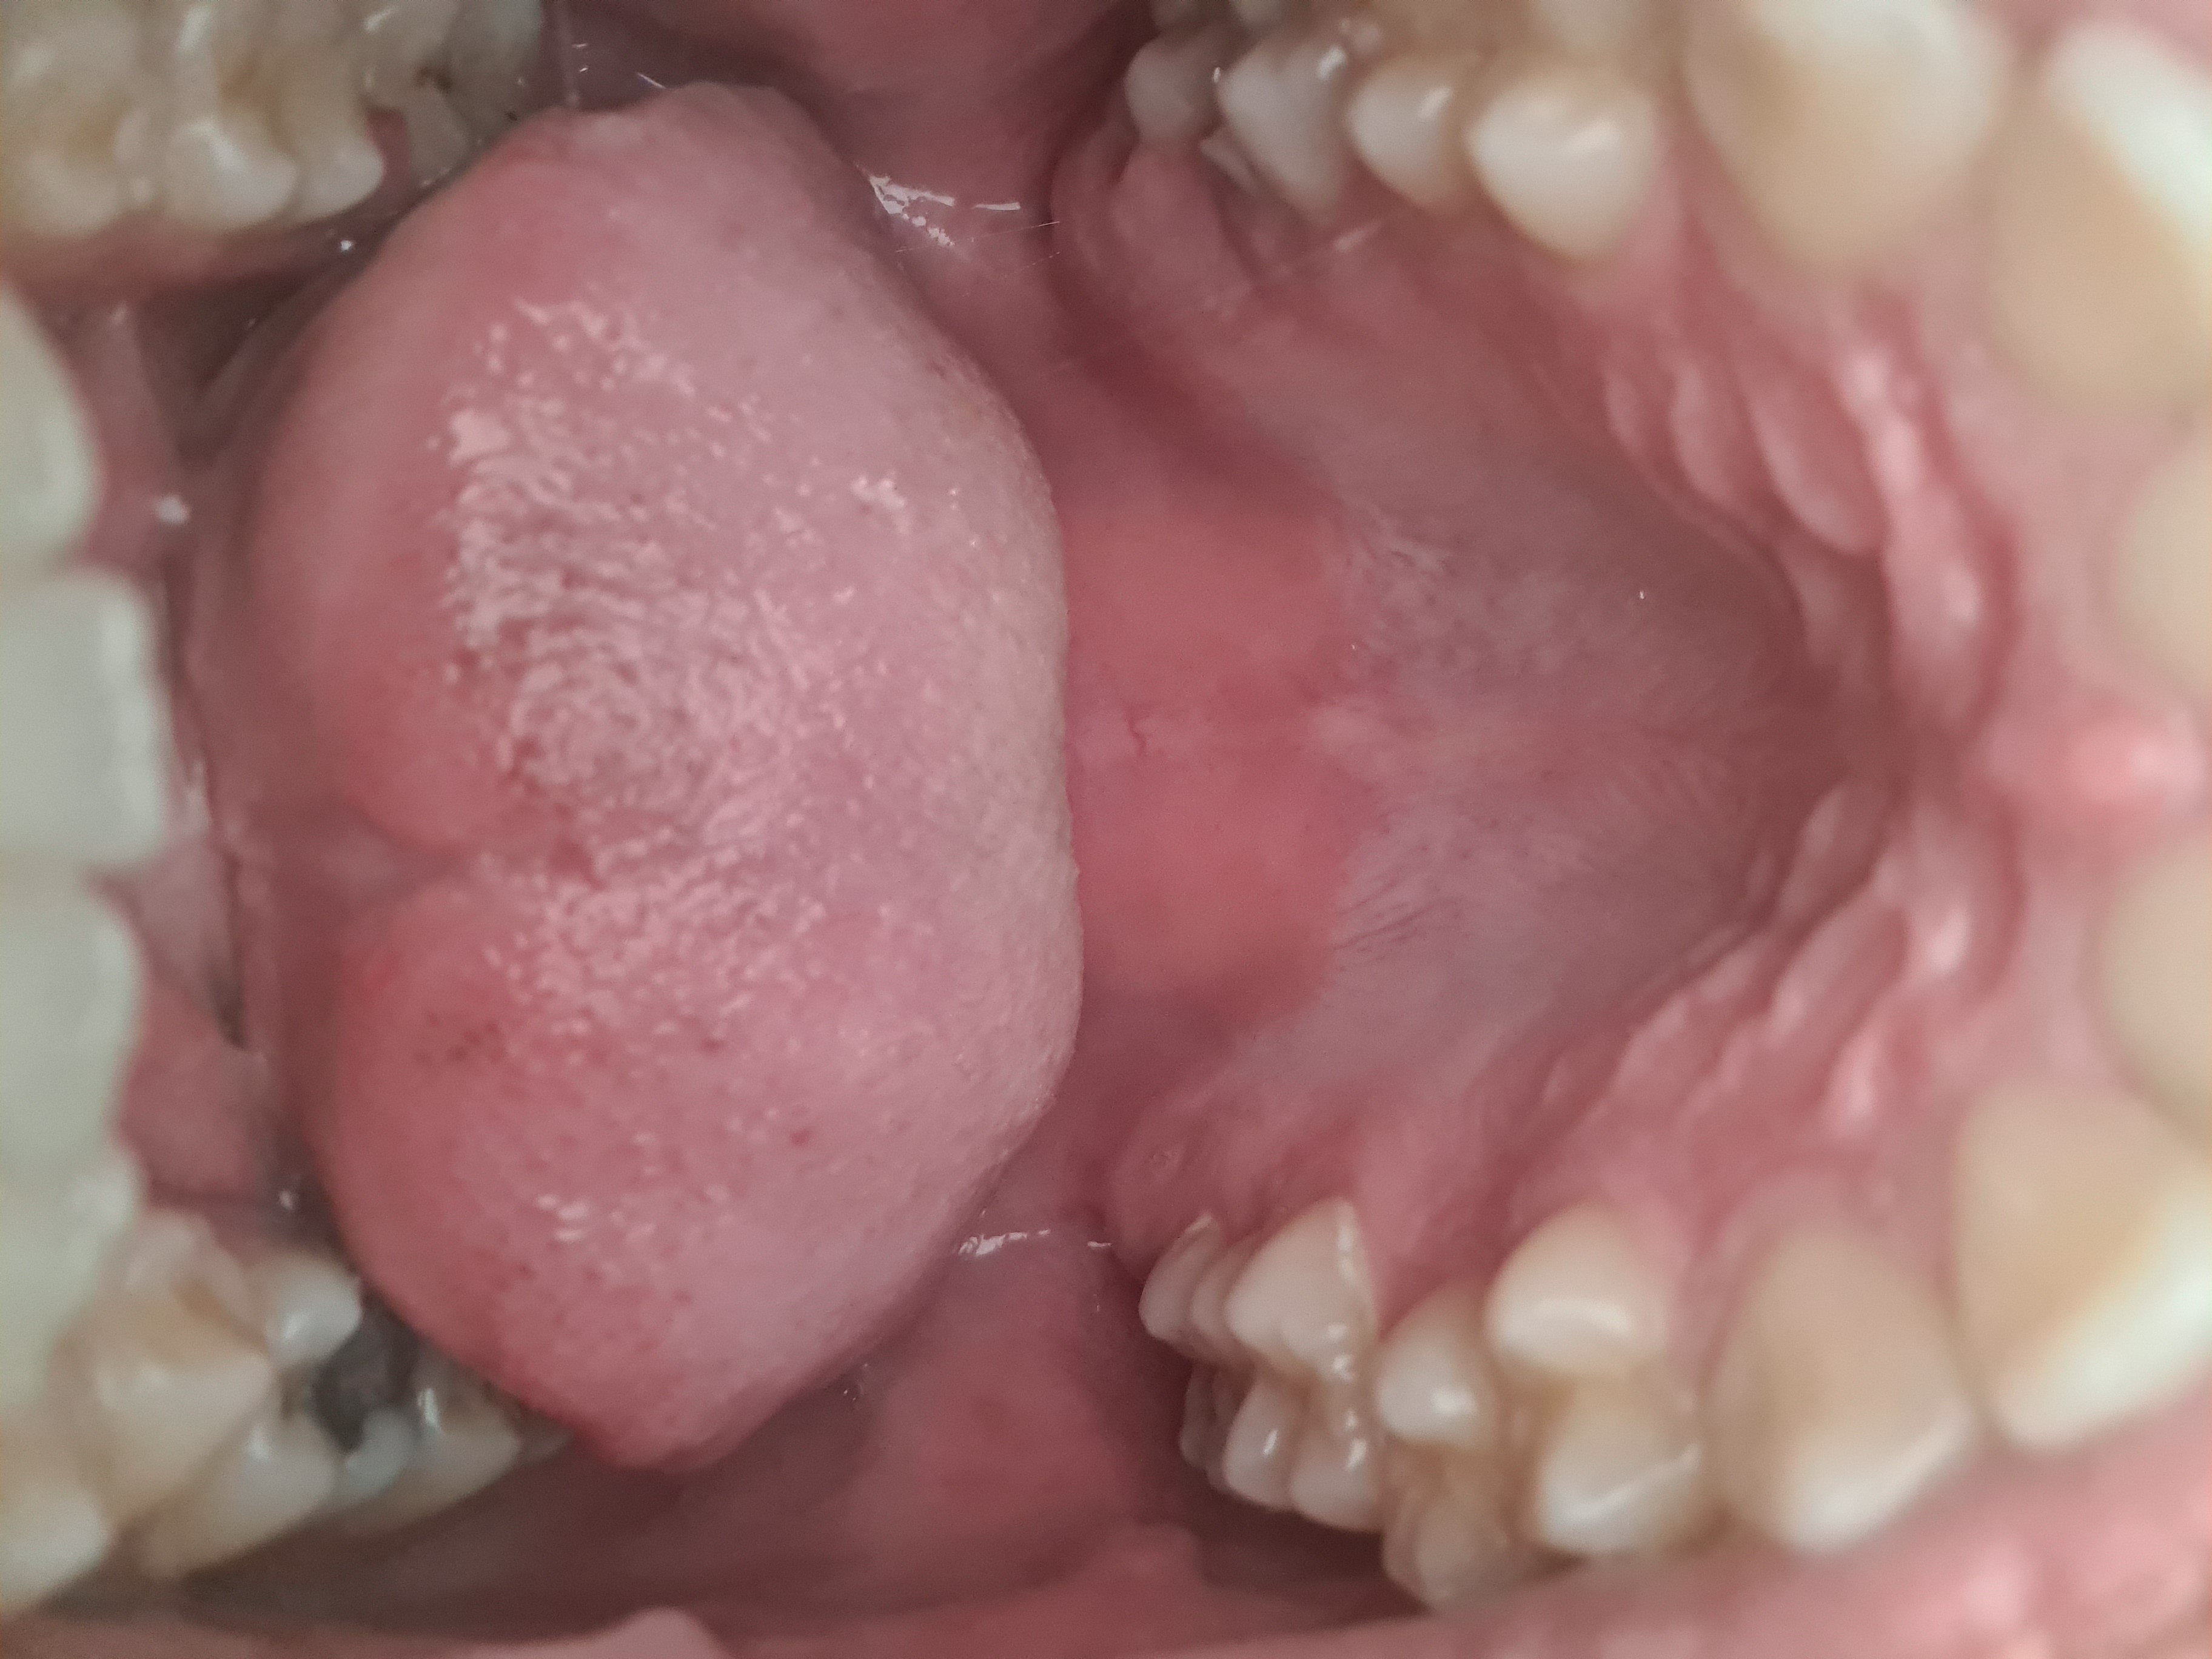

palate (i think medium, slightly narrow) and the black think is a piece of metal not decaying.

im pretty sure i have an overjet

your mandible is severely recessed

try for BSSO

your overlapping seems to 8-13mm range ig

are your upper teeth inclined outwards?

for accurate answers you'd need to get a cephalometric analysis bro

then check relation between maxilla (SNA) and mandible (SNB) relative to cranial base.

If SNB is, say, 84°, it's a hyper divergent pattern so mandible is normal (great, actually). Which means your bite difference is most definitely due to upper incisors inclining outwards

If SNB, is, say, 70°, it's skeletal retrognathia and you'd 100% need a BSSO

rn I'm confused as to which case you are. getting a bsso with normal mandible but extremely proclined incisors would fuck you up.